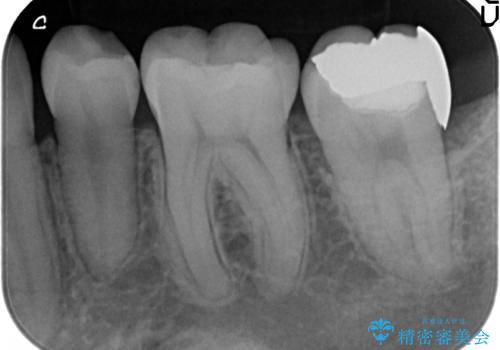

- 左下7の銀歯を白くしたいといらっしゃった方の症例です。

左下7遠心(下記のX線写真の左側)の歯質が歯肉縁下でかつポケットも深かったため、歯茎を下げる歯周外科を行いました。